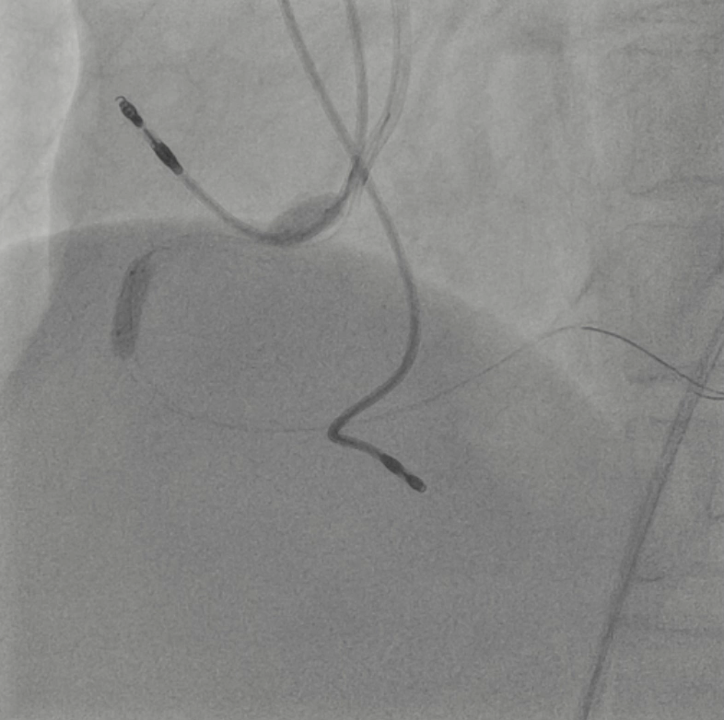

A 7Fr guiding catheter (GC) was insertedvia the right femoral artery. The lesion was crossed using a floppy wire, and intravascularultrasound (IVUS) revealed a severe stenosis caused by a non-calcified plaque.The lesion was dilated using a scoring balloon. Subsequent IVUS showed an intimaldissection at the RCA ostium. To cover the initial dissection, a drug-elutingstent was deployed from the RCA ostium, followed by post-dilation with a 3.75mmnon-compliant balloon (NCB) inside the stent. IVUS demonstrated proximal stentelongation with approximately 5 mm aortic protrusion from the RCA ostium. Stentpush from the aorta using a 5.0 mm NCB, however, the GC was crushed due toinsufficient backup support. The recrossed wire passed through the side of thestent struts, and even with the knuckle wire technique, it could not beadvanced through the central lumen of the stent. IVUS was advanced thorough thiswire, and another floppy wire was successfully reinserted into the stent fromthe stent edge using the tip detection method. Another wire was placed in theRCA using a double-lumen catheter, and the anchor balloon technique wasperformed in the middle-part of the RCA with a 3.75mm NCB. Then, the stent pushtechnique was performed using a 5.0 mm NCB to shorten the elongated stent,followed by post-dilation of the proximal stent with the 3.75mm NCB. IVUSconfirmed successful stent shortening, with approximately 1.2mm of stentprotrusion into the aorta, which was acceptable.

We report a case of protruding stent at theright coronary ostium that was rewired by the tip detection method and adjustedwith the stent push technique using a large balloon. The IVUS-guided tipdetection method was useful for guiding the wire into the inside of the stent.Accurate positioning of aorto-ostial coronary stents is technically difficult,so it is sometimes unavoidable for stent protrusion. However, stent pushtechnique can be an effective method for adjusting stent protrusion to theaorta.